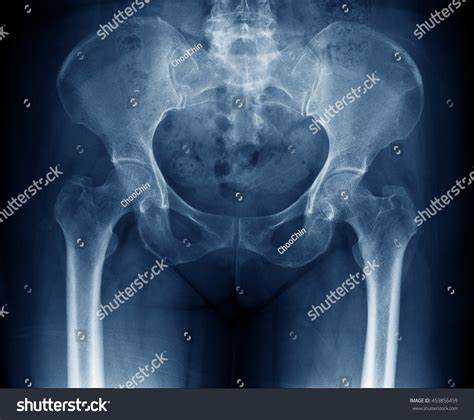

Normal Hip X Rays are a type of radiographic imaging used to visualize the hip joint and surrounding structures. This non-invasive procedure helps diagnose a wide range of conditions, including fractures, dislocations, arthritis, and developmental issues. The hip joint is a complex structure composed of the femoral head, acetabulum, and supporting ligaments and muscles. Normal Hip X Rays provide a clear view of these components, aiding in accurate diagnosis and treatment planning.

Interpreting Normal Hip X Rays requires a trained eye and a thorough understanding of hip anatomy. Radiologists look for specific features and measurements to determine the health of the hip joint. Key areas of focus include:

• Bone Density: Normal bone density indicates healthy bone structure. Any areas of decreased density may suggest osteoporosis or other bone diseases.

• Joint Space: The space between the femoral head and the acetabulum should be uniform and well-defined. Narrowing of this space can indicate arthritis or other degenerative conditions.

• Alignment: Proper alignment of the femoral head within the acetabulum is crucial. Misalignment can suggest dislocations, fractures, or developmental issues.

• Soft Tissue: While X-rays primarily focus on bone structures, they can also reveal abnormalities in soft tissues, such as swelling or calcification.